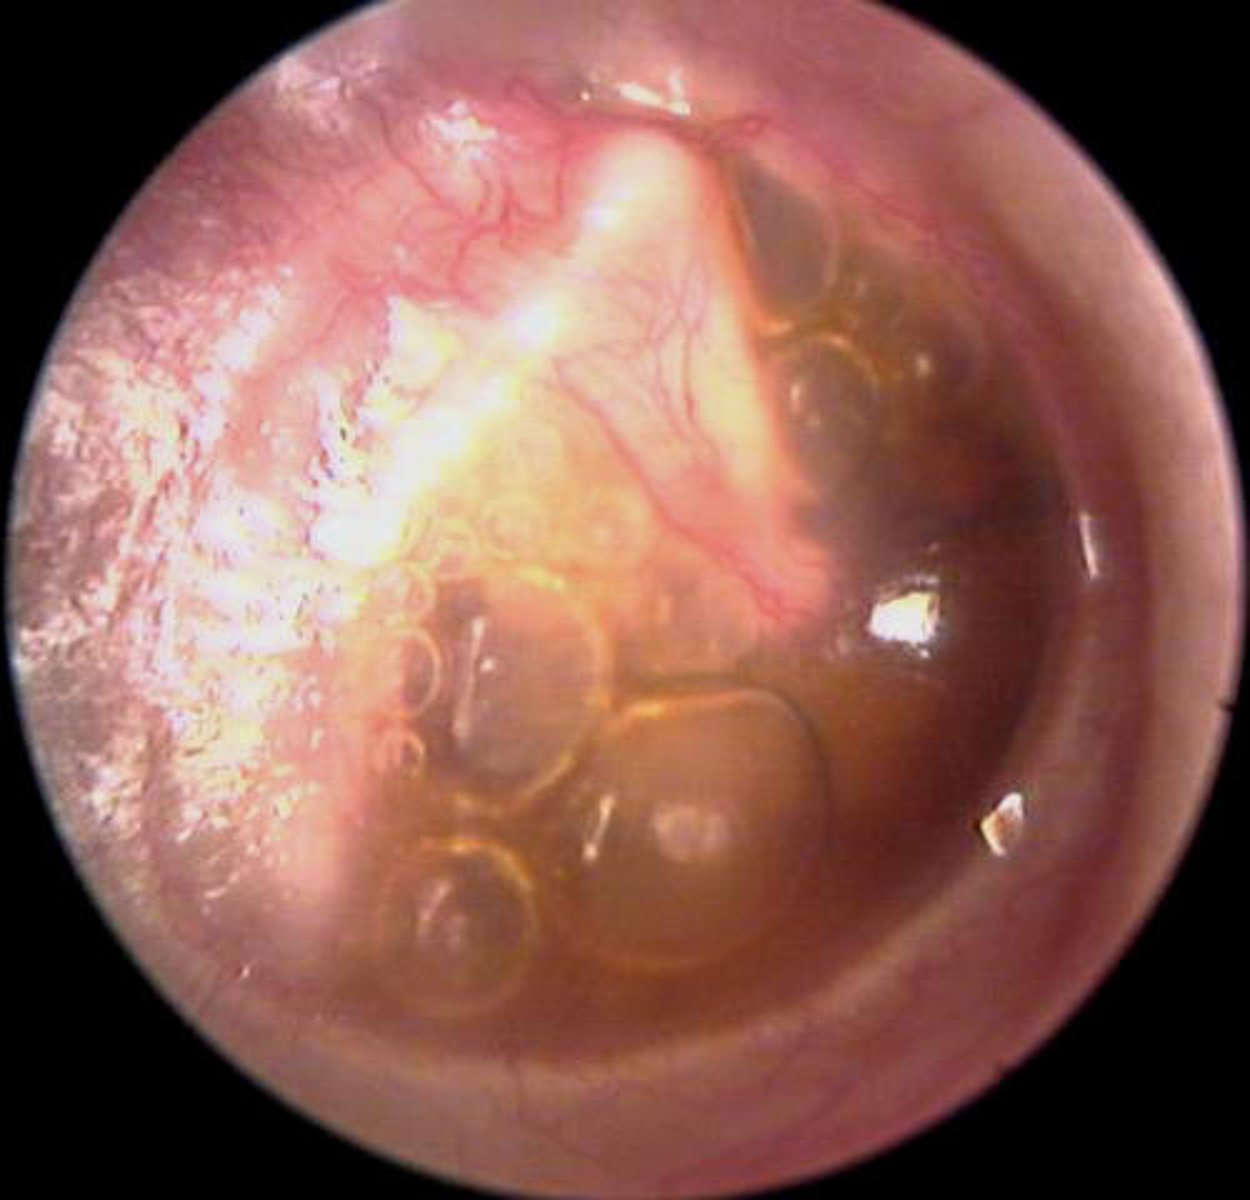

otitis media with effusion

NOT INFECTED

Cracking when yawning

Discomfort/aural fullness

Conductive HL dt to fluid

TM retracted with air bubbles

<p>NOT INFECTED</p><p>Cracking when yawning</p><p>Discomfort/aural fullness</p><p>Conductive HL dt to fluid</p><p>TM retracted with air bubbles</p>